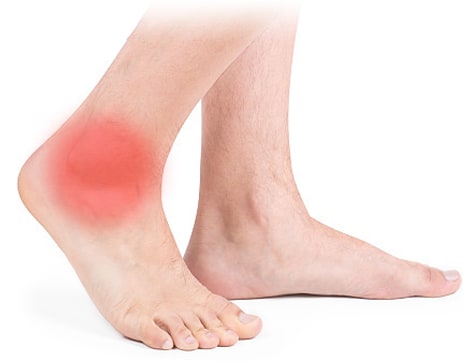

관절에 염증이 생기면 주변의 혈관이 확장되어 더 많은 혈액이 관절에 도달하게 됩니다

관절이 뜨겁거나 고통스러울 수 있으며 염증은 근본적인 손상이나 감염의 통증을 심화시킬 수 있습니다.

관절염 초기에는 경미한 통증이 나타나지만 휴식 시에는 통증이 줄어들게 됩니다. 날씨가 춥거나 습한 날씨에 더욱 통증이 악화되는 경우가 있습니다. 점점 진행되면서 관절의 붓고 움직임 시 통증이 나타나기 때문에 관절 운동 범위가 제한되게 됩니다. 운동 시에도 피로감을 쉽게 느끼게 됩니다. 또한 초기에는 관절 경직이 나타나서 관절염이 진행될수록 관절 내 통증으로 인해 관절의 움직임 제한이 심해지게 됩니다.

근육의 위축과 관절의 구축은 관절의 기형을 유발하게 되며, 관절의 연골이 닳아서 관절에 소리가 날 수 있습니다. 또한 관절의 열이 나거나 발적이 나타날 수 있고 관절이 변형되어 굽은 다리로 진행될 수 있습니다.

지속적인 염증이나 통증을 느끼는 사람들은 관절염이 있을 수 있습니다. 열이 나거나 감염 후 발생하는 관절통은 즉각적인 치료가 필요한 관절염의 신호일 수 있습니다